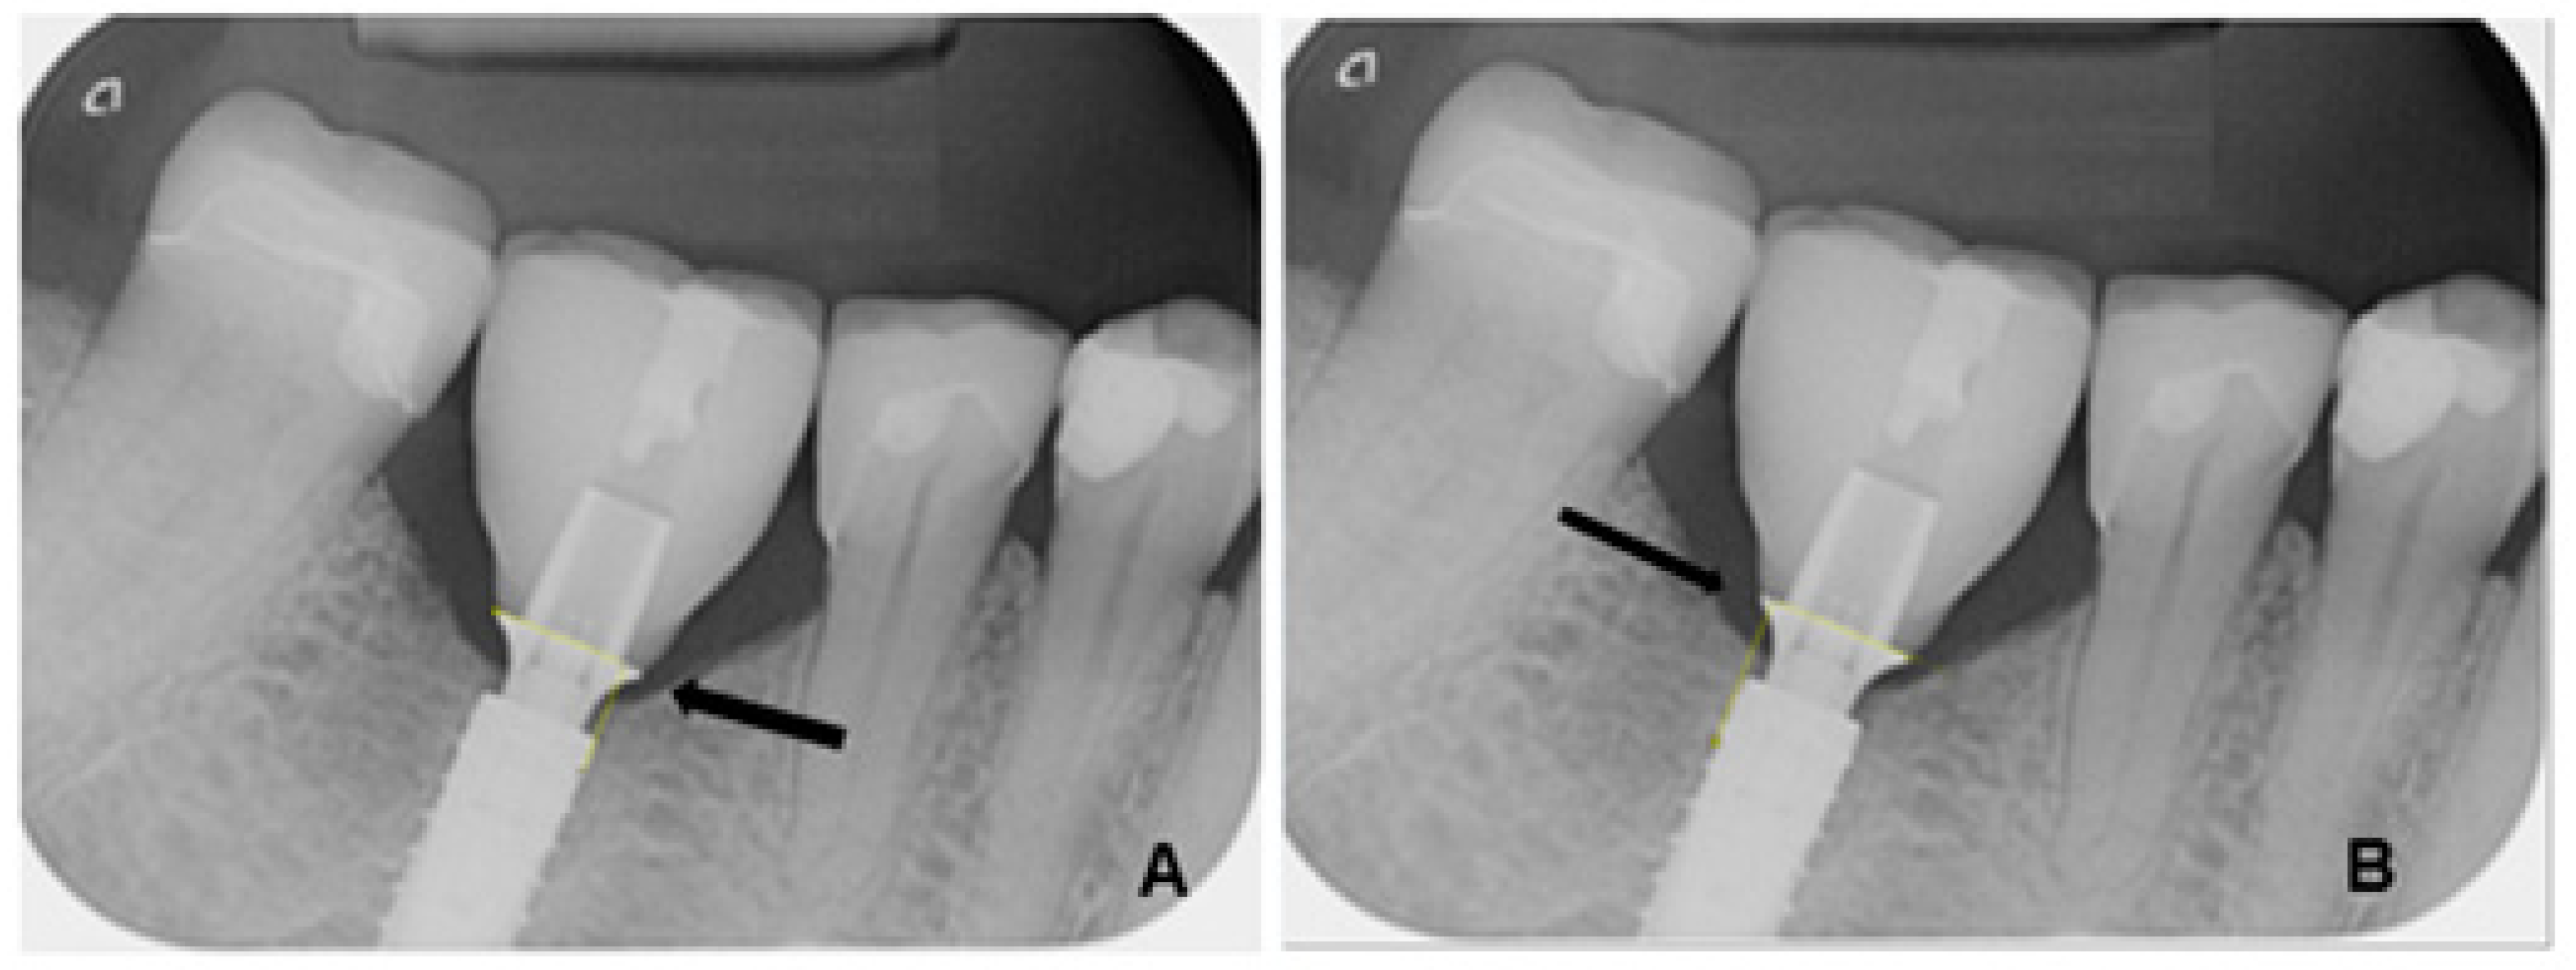

- Damage to the implant-abutment complex (Figure 2);

- Loosening or fractures of abutment screws.